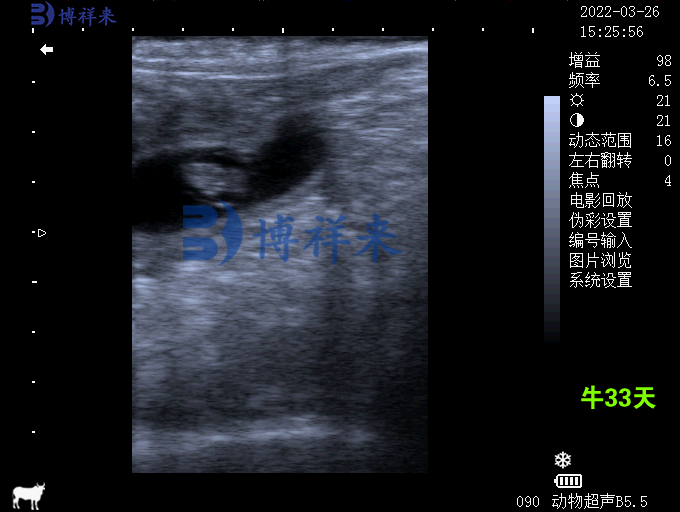

- 牛类(奶牛、肉牛、水牛): 是兽用B超机应用***成熟的领域,主要用于规模化牛场的繁殖管理。

- 子宫状态: 判断早期妊娠(测孕)、子宫炎症及积液。

- 卵巢发育: 观察卵泡大小、黄体结构,精准掌握发情期,提高受孕率。